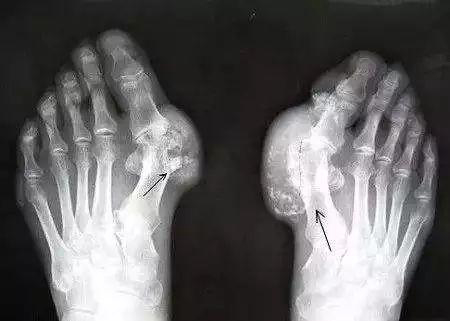

疗法治疗对象:各种痛风剧痛难忍。